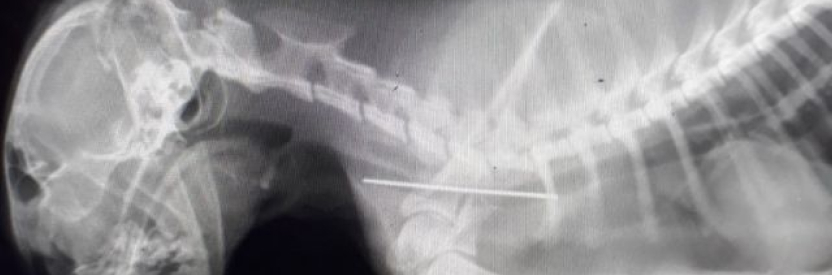

Рентгенография — основной метод поиска металлических предметов. Игла видна на снимках как тонкая линия, но при нахождении в кишечнике ее положение может меняться каждые несколько часов, поэтому иногда требуется серия снимков с интервалом.